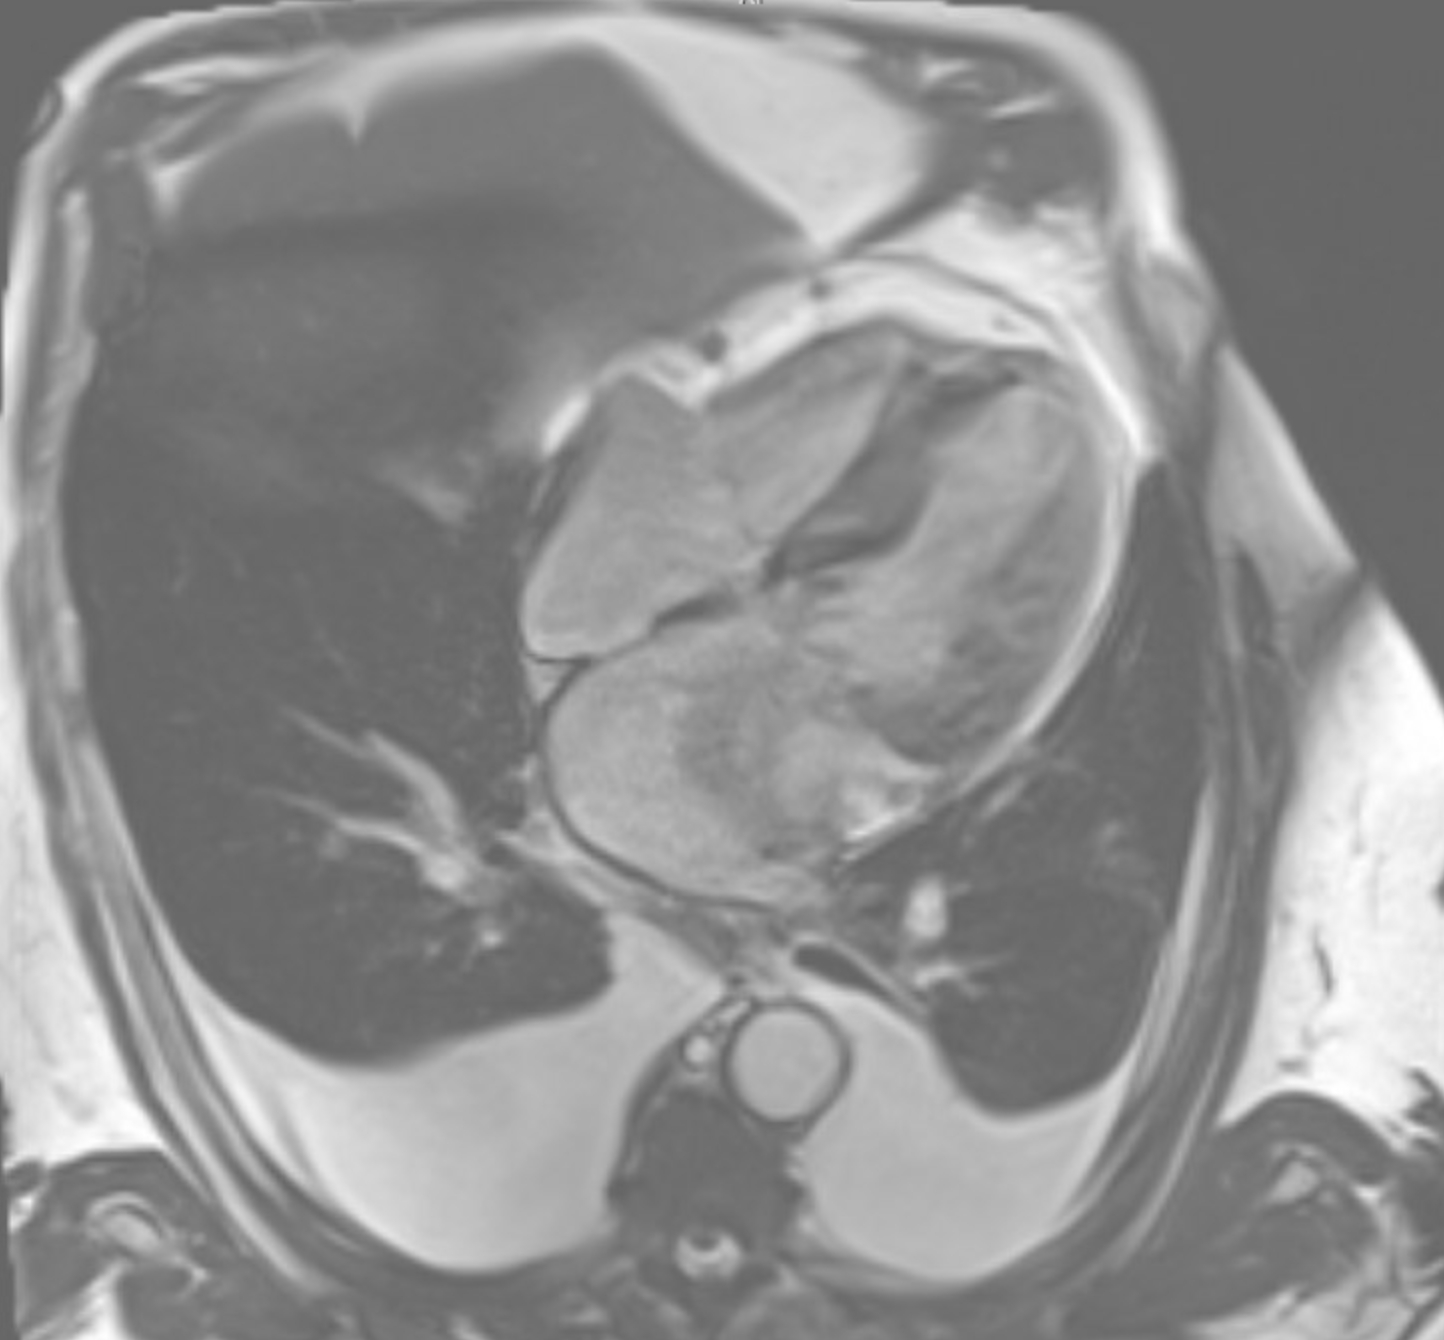

Case Description: An 81-year-old male with multiple comorbidities including hypertension, atrial fibrillation, bioprosthetic aortic valve replacement (2022), Crohn's disease, and HFmrEF presented with gastrointestinal symptoms. CT abdomen incidentally revealed a large pericardial mass (10×7 cm) compressing the left atrium and basal left ventricle, causing severe mitral stenosis (mean gradient 15 mmHg). Initial differential included mesothelioma and metastatic pulmonary sarcomatoid carcinoma. The patient underwent 10 sessions of palliative radiation. Post-radiation, he developed worsening nausea, vomiting, dysphagia, atrial fibrillation with RVR, and pleural effusions. Cardiac imaging (MRI [Figure 1] and PET [Figure 2]) confirmed the pericardial mass with compression effects and no distant metastases. Thoracentesis and supportive care provided temporary relief. Pericardial FNA pathology revealed a biphasic keratin-positive malignant neoplasm consistent with sarcomatoid carcinoma. Immunohistochemistry was positive for AE1/AE3, CK7, vimentin, and OSCAR. Negative markers ruled out mesothelioma, RCC, melanoma, and other sarcomas. Despite multidisciplinary input, the mass was inoperable. Planned AV nodal ablation and Micra pacemaker were deferred due to anesthetic risk. Inpatient chemotherapy (carboplatin + pemetrexed) was planned, but the patient decompensated before initiation.

Discussion: Sarcomatoid carcinoma of pericardial origin is undocumented. PET/CT imaging and immunohistochemistry were key to diagnosis. Tumor compression mimicked valvular and heart failure symptoms, complicating management. Despite early multidisciplinary care, prognosis was poor due to rapid clinical decline.